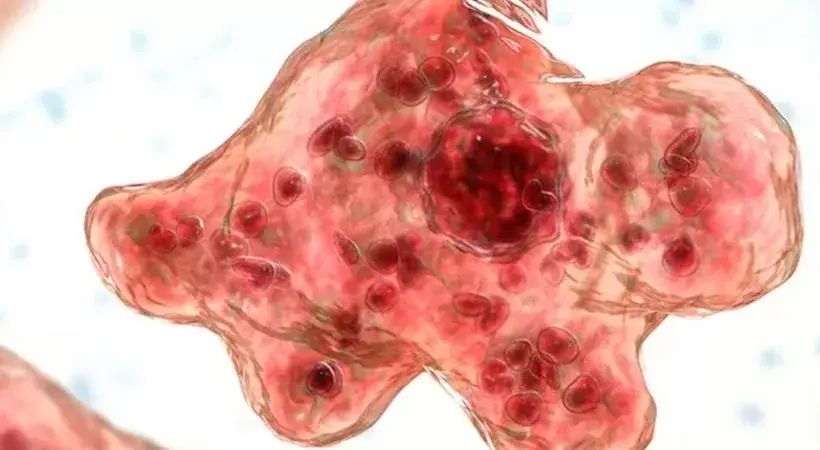

എന്താണ് അമീബിക് മസ്തിഷ്കജ്വരം?

തലച്ചോറിനെ ബാധിക്കുന്ന അപൂർവവും എന്നാല് ഗുരുതരവുമായ ഒരു രോഗമാണ് അമീബിക് മസ്തിഷ്കജ്വരം. ജലത്തില് കാണപ്പെടുന്ന നെഗ്ലേറിയ ഫൗളേറി (Naegleria fowleri) എന്ന അമീബയാണ് ഈ രോഗത്തിന് പ്രധാന കാരണം. മലിനമായ കുളങ്ങളിലോ, പുഴകളിലോ, കെട്ടിക്കിടക്കുന്ന വെള്ളത്തിലോ കുളിക്കുമ്ബോള് ഈ അമീബ മൂക്കിലൂടെ ശരീരത്തില് പ്രവേശിക്കുന്നു. ഇത് പിന്നീട് തലച്ചോറിലെത്തി അണുബാധയുണ്ടാക്കുന്നു.

മൂക്കിനേയും മസ്തിഷ്കത്തേയും വേർതിരിക്കുന്ന നേർത്ത പാളിയിലുള്ള സുഷിരങ്ങള് വഴിയോ കർണ പടലത്തിലുണ്ടാകുന്ന സുഷിരം വഴിയോ അമീബ തലച്ചോറിലേക്ക് കടക്കുകയും മെനിഞ്ചോ എൻസെഫലൈറ്റിസ് ഉണ്ടാക്കുകയും ചെയ്യുന്നു. 97 ശതമാനത്തിലധികം മരണനിരക്കുള്ള രോഗമാണിത്.രോഗം മനുഷ്യരില്നിന്നു മനുഷ്യരിലേക്ക് പകരില്ല.